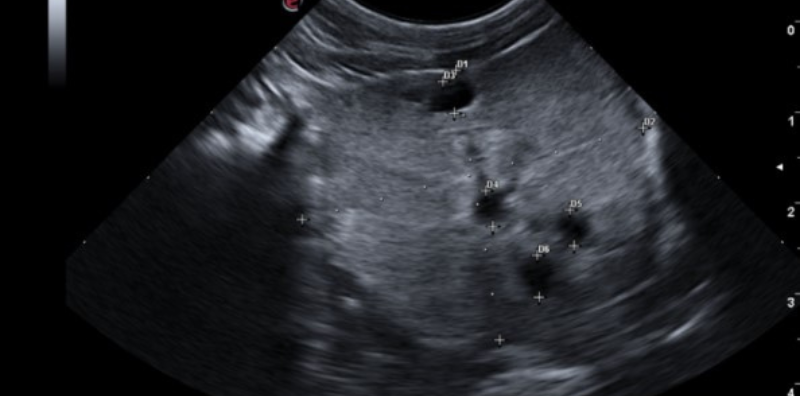

- Ecografía: detecta quistes o tumores y permite tomar muestras para biopsia.